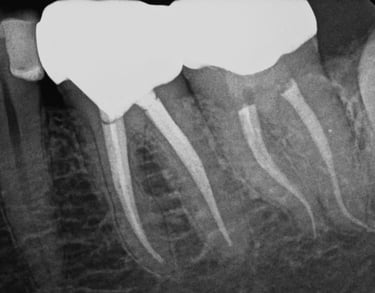

Cuando una caries profunda o un traumatismo alcanzan el nervio dental, es necesario realizar una endodoncia para conservar la pieza.

En IdenClinic eliminamos el tejido infectado del interior del diente y sellamos los conductos radiculares con máxima precisión, utilizando instrumentación rotatoria y control digital de longitud.

Este procedimiento detiene la infección, alivia el dolor y evita la extracción. Posteriormente, reforzamos el diente con una reconstrucción o corona protectora, devolviéndole su funcionalidad y aspecto natural para una salud bucal a largo plazo.

ENDODONCIA